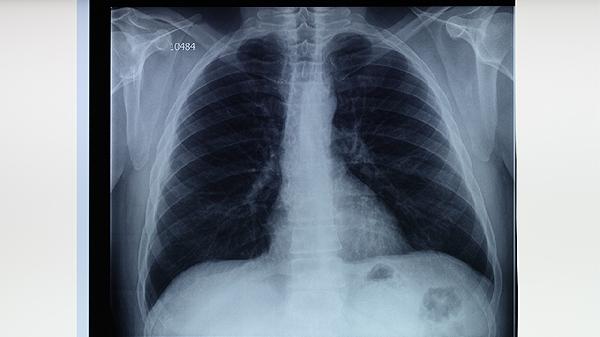

5、就医建议:如果对肺结核的传染性有疑虑,建议咨询专业医生进行评估。医生可以通过痰液检查、胸部X光等手段,判断患者的病情状态和传染风险。及时就医和遵循医生的建议,是预防疾病传播的关键。